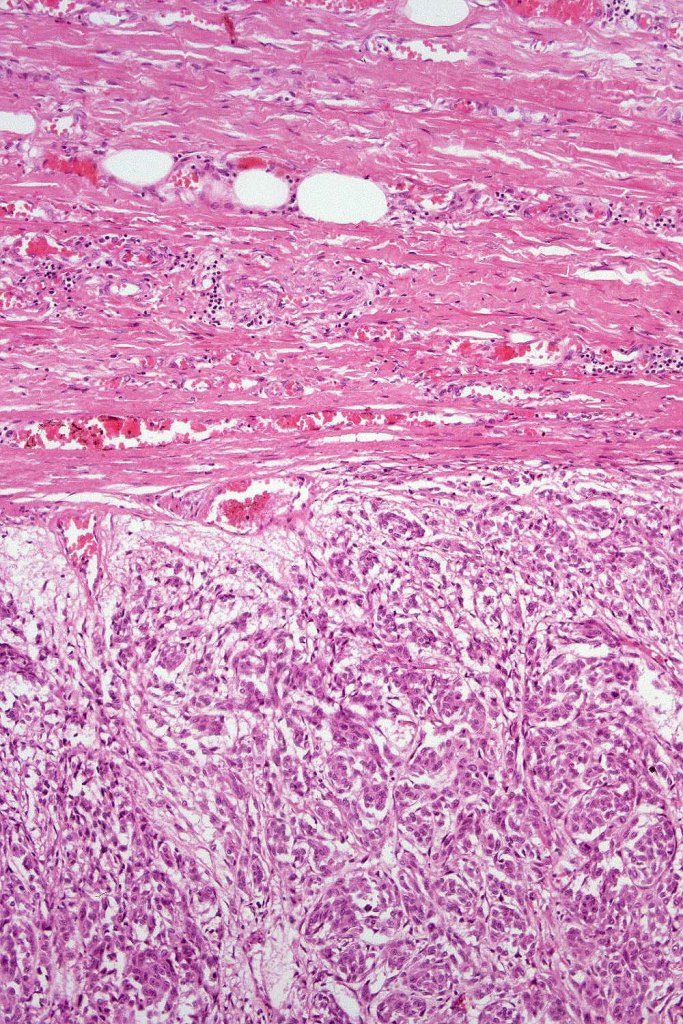

All of the cases that I have personally encountered have been metastases.

In this example, rhabdoid change accounted for only a small component of the tumor. IHC is S100